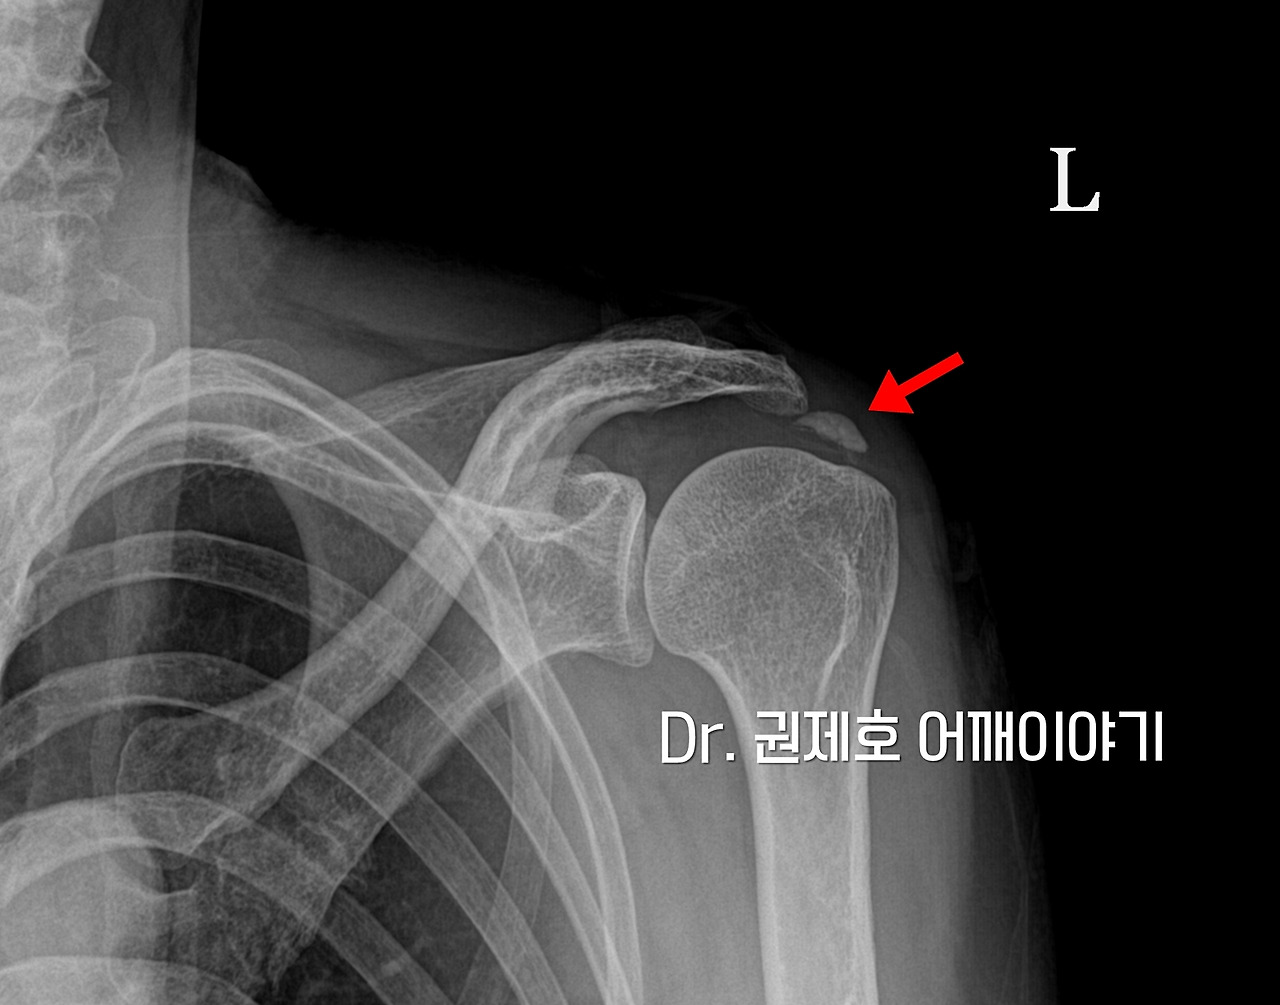

X-ray

외래에 왔을 때 엑스레이를 찍었다. 누가 봐도 어깨석회성건염이다. 그 크는 작지는 않았다.